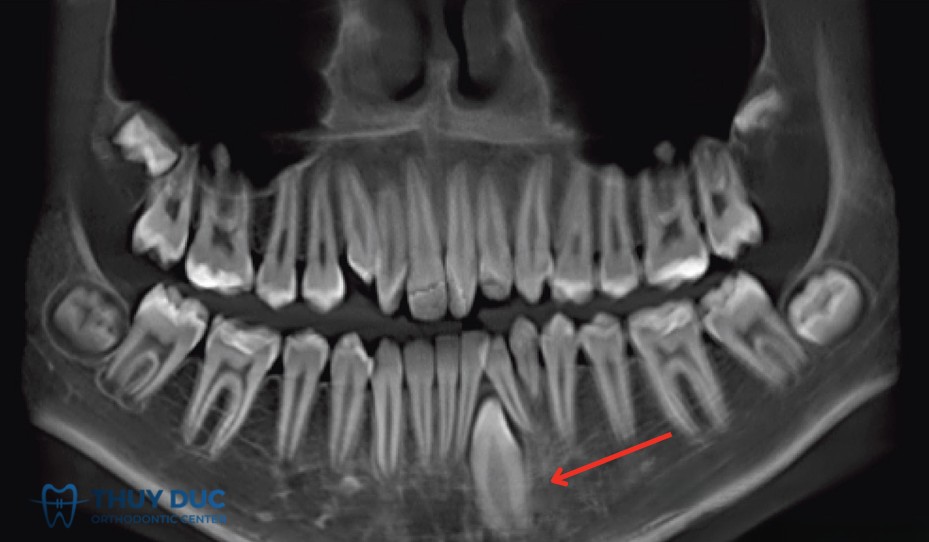

Vì vậy, phương pháp chẩn đoán chính xác nhất là chụp X-quang (thường là phim panorama hoặc phim cận chóp). Trên thực tế, rất nhiều bệnh nhân chỉ phát hiện mình có răng mọc ngầm khi đi khám và chụp phim để điều trị một vấn đề khác, ví dụ sâu răng, viêm nha chu hoặc chuẩn bị niềng răng.

2.4 Răng hàm nhỏ mọc ngầm

Răng hàm nhỏ nằm giữa răng nanh và răng hàm lớn. Mọc ngầm ở nhóm răng này thường liên quan đến thiếu chỗ hoặc do răng sữa bị mất sớm khiến răng kế cận dịch chuyển, làm cản trở đường mọc. Trường hợp này nếu không xử lý kịp có thể làm lệch toàn bộ khớp cắn.